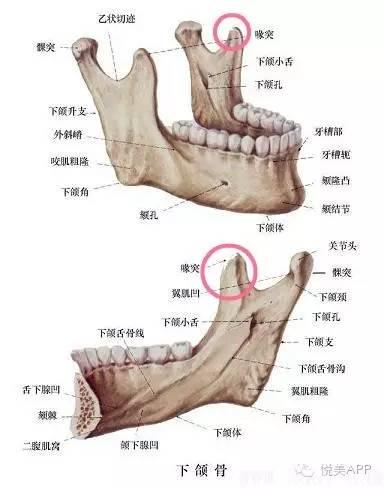

颧骨内推是有一定限度的,颧弓内推的极限决定于颧弓和下颌骨喙突之间的距离,颧弓内推只要不妨碍下颌骨喙突的运动,可以达到极限值。

下颌骨喙突位置:

也就是白色圆圈内的两块骨头距离,推太多会导致张口受限,影响功能